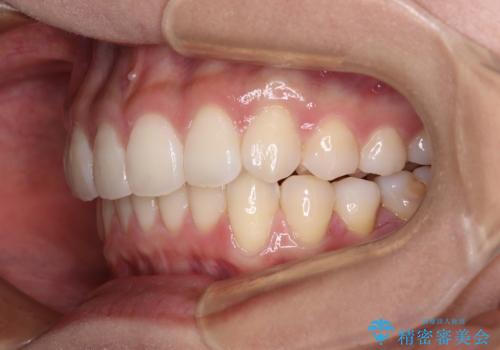

- 前歯のデコボコを治したいとのことで来院された患者様です。

上下顎ともに歯列全体の後方移動とIPR(歯と歯の間を削る)によってデコボコが解消するように設計し、インビザラインにより治療を行うこととしました。